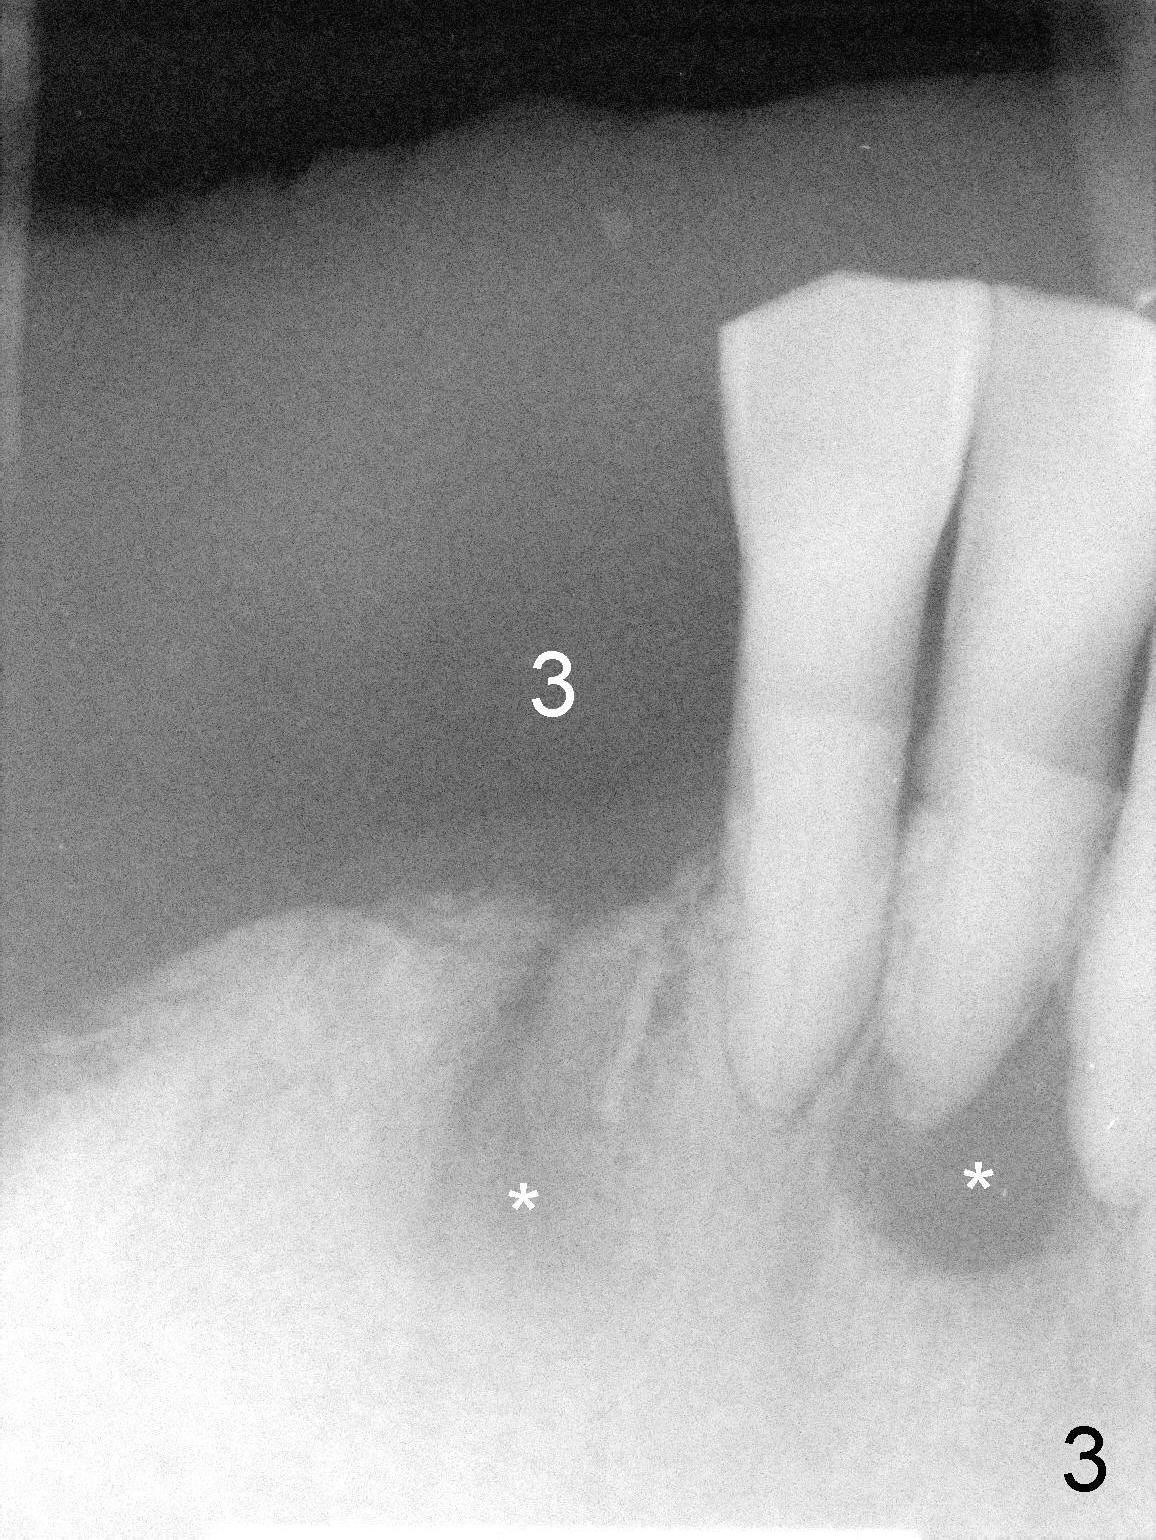

The lower right bridge (from canine (Fig.2: 3) to 1st molar (Fig.1: 6)) fails while a 77-year-old man is undergoing chemotherapy for urinary bladder cancer.  The abutments of the bridge are extracted without plan for implants (Fig.4).   Four months later, the patient returns for implants (Fig.3), but the ridge is narrow (Fig.5).  While 2 of 3x14 mm 1-piece implant are placed at the canine and 1st bicuspid sites, 2 piece ones at the 2nd bicuspid and 1st molar sites (Fig.6: 3.5x11 mm, 5x14 mm).  Soft (Fig.7-10) and hard (Fig.11) tissues heal 1 week (Fig.7) and 4 months (Fig.8-11).  There is minimal bone resorption 1 year 7 months post cementation (Fig.12,13, non-splinting).  It appears that narrow diameter implants are a valid solution to narrow ridge at the sites of the lower canine and premolar.  As long as there are enough implants for function, the crowns are not necessary to be splinted.  Surprisingly, the patient starts flossing after implant restoration.  Retrospectively an immediate provisional bridge should have been fabricated.